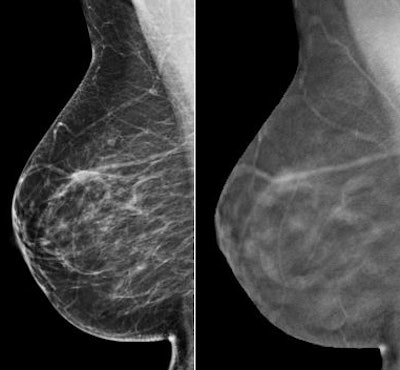

| Right breast mediolateral oblique 2D view (left) shows a spiculated asymmetry at middle depth. Right breast mediolateral oblique tomosynthesis view (right) shows the asymmetry is superimposed tissue. Images courtesy of Yale School of Medicine. |

"Similar recall rates were seen in both groups for masses," Durand said. "However, the recall rate was only 2.8% for asymmetries when digital tomosynthesis was added, compared to 7.1% when only mammography images were viewed."

"One of the many benefits of tomosynthesis is that breast imagers can scroll through breast tissue," Durand added. "Instead of being faced with an asymmetry on 2D mammography that you're unsure of, if tomosynthesis is available, many times that area will be spread out during the scroll-through, and it will be possible to confidently assess it as normal superimposed tissue."